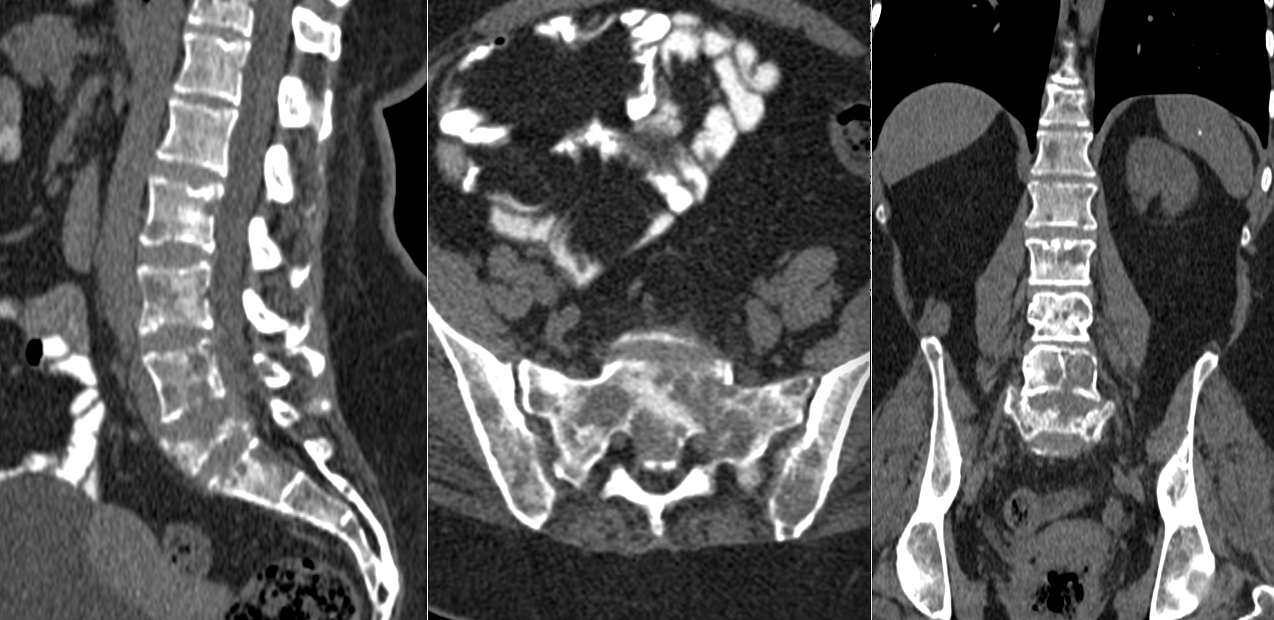

Pe măsură ce tumora crește, osul se subțiază, se fragilizează și poate ceda, ducând la tasări sau fracturi vertebrale.

- distruge progresiv corpul vertebral

- slăbi structura osului

- produce tasări sau colaps vertebral

Diagnosticul tumorilor spinale osoase se bazează pe imagistică de înaltă performanță. Rezonanța magnetică este investigația principală, deoarece oferă informații detaliate despre os, măduvă și nervi. Tomografia computerizată este utilă pentru evaluarea distrugerii osoase.